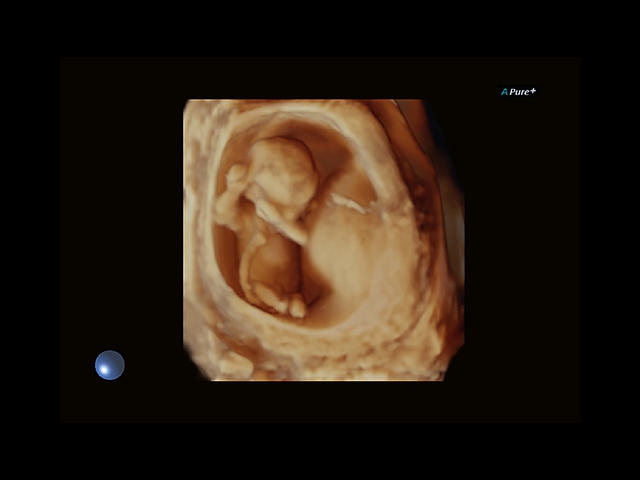

Aplio 500 – ультразвуковой сканер премиум класса, сочетающий в себе быстродействие диагностики и отличное качество визуализации. Более 30 датчиков на выбор, в т.ч. матричные, монокристаллические, 4D, эндоскопические для любых типов исследований. Ультразвуковой сканер позволяет изучать анатомические структуры в высоком разрешении.

Обновленная версия легендарного УЗ-сканера. Стационарный аппарат экспертного класса Aplio 500 Toshiba NEW, визуализирует анатомические структуры в высоком разрешении. Модель позволяет выявить микрокальцификаты, новообразования, нарушения в работе сердца, сосудов и мышц. Присутствует функция виртуальной эндоскопии, 4D-сканирования, эластометрии тканей, УЗИ с контрастированием. За повышение качества изображения отвечают технологии ApliPure и Superb Microvascular Imaging. Первая задействует возможности пространственного и частотного кодирования, формирует цельный визуальный ряд с сохранением клинических маркеров. Вторая улучшает отображение микрососудистого русла, используя доплеровский эффект. Модель оснащена 21-дюймовым монитором, имеет 4 активных порта. Возможно подключение педиатрических, интраоперационных, лапароскопических и чреспищеводных датчиков.

4D: